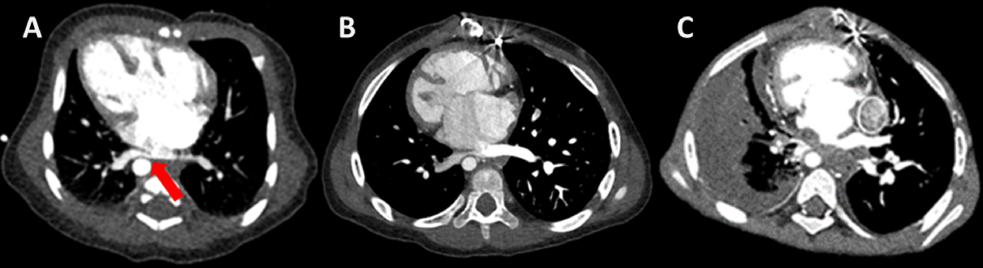

Fig. 1 Image of contrast-enhanced computed tomography

(A) Image of contrast-enhanced computed tomography on day 8. The right lower pulmonary vein was compressed by the descending aorta and atrium (arrow). (B) Image of contrast-enhanced computed tomography before Fontan procedure. The right lower pulmonary vein stenosis was still present. (C) Image of contrast-enhanced computed tomography 3 month after Fontan procedure. The right lower pulmonary vein was occluded and a large amount of pleural effusion was appeared.

胎児エコーで先天性心疾患が疑われ当院にて管理を行った.在胎40週6日,2,964 gで出生し上記のように診断した.日齢8の造影CTで右下肺静脈が下行大動脈から圧迫され(Fig. 1A),将来的に同部位の閉塞を起こす可能性があった.

その後は共通房室弁閉鎖不全の増悪なく成長発達が得られた.2歳2か月時にFontan手術前評価として心臓カテーテル検査などの精査を行った.心臓カテーテル検査は両側の平均肺動脈圧は8,平均下大静脈圧は5,右室容積は109% of normal, RVEFは59%,PA indexは251であった(Table 1).上大静脈造影で右肺動脈への順行性血流を認め,体肺側副血管の発達は左右差を認めなかった.造影CT検査で右下肺静脈狭窄を(Fig. 1B),心エコー検査では共通房室弁閉鎖不全を認めた(Fig. 2A).

術後2か月まで肺うっ血を認めなかったが,術後3か月で発熱,多呼吸,咳嗽や頻脈が出現した.胸部レントゲンで右肺うっ血と胸水を認め,造影CTで右肺静脈閉塞と肺炎所見を認めた(Fig. 1C).心臓血管外科と協議し,右肺静脈は心膜外で狭小化を認め,かつ末梢側まで細く修復は困難との結論に達した.抗菌薬に反応なく胸水が増加したため右胸腔ドレナージを行った.胸の培養検査や細胞診で異常所見なし.利尿剤の増量を行い徐々に胸水は減少し退院した(2歳11か月).